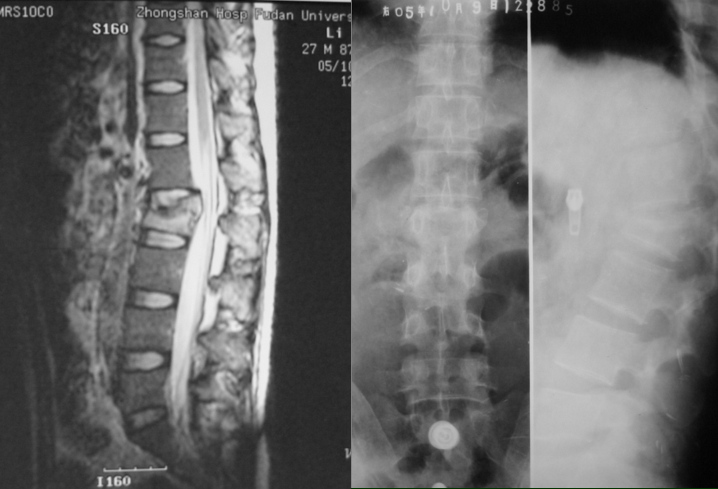

陈旧性爆裂骨折

• 残留神经症状

• 两年以内

• 翻修手术仍然有效

内固定失败翻修病例患者,女性,腰1爆裂骨折

术前CT可见骨折块明显压迫脊髓

术后X线表现,可见1枚螺钉打入椎间隙,钛网位置好。

术后MRI,脊髓减压彻底

术后半年,隐约可见钛网下陷

术后1年,钛网下陷、松动,钢板也明显松动。

翻修后的X线表现